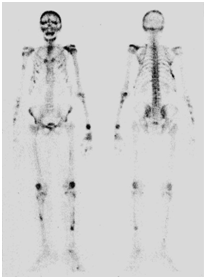

A 64-year-old man, without significant medical history, presented with multiple bone pain.These pains were not calmed by analgesics. The general condition was maintained and physical examination was normal. There were no clinical signs of Hypercalcemia (polyuria, gastrointestinal symptoms). Biology showed calcium at upper limit level: 2.66mmol/l (the reference range for the laboratory was 2.2-2.6mmol/l). We did X-rays analyses and a CT-scan that showed multiple lytic lesions especially on peripheral bones (Figure 1). Secondary bone metastases were suspected therefore bone scintigraphy was indicated. He did a Tc-99m MDP whole body bone scan which showed multiple areas of intense uptake, within both axial and peripheral skeleton, on the same sites of lytic lesions found on X-rays analyses and CT-scan (Figure 2). That aspect recalls the aspect of disseminated brown tumors, so we dosed the PTH in serum, which was very high: 2003µg/l (the reference range for the laboratory was11-62µg/l).

Figure 1 X-rays analyses showing lytic lesions on peripheral bones.